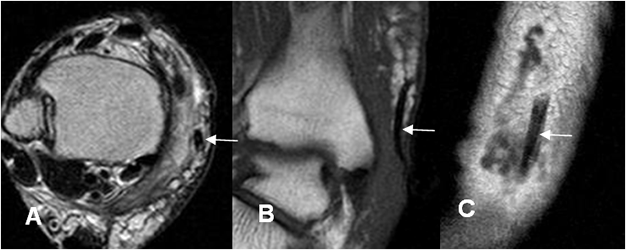

Fig 123. Cuerpo extraño.

A: RM axial en T2. Cambios inflamatorios en el tejido celular subcutáneo, el cual es hiperintenso en T2.

B: RM coronal y C: RM sagital en T1. Existe imagen lineal y alargada, hipointensa en todas las secuencias, que corresponde a cuerpo extraño, el cual desencadenó la infección.